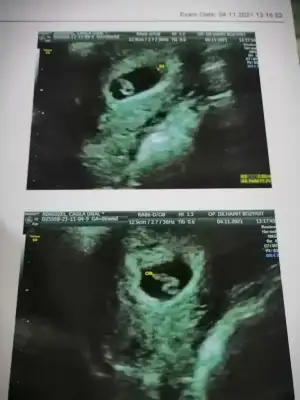

Evet canım, iki kese gördük dün. Şok oldumŞuan ikiz mi yoksa?![]()

Evet canım, iki kese gördük dün. Şok oldum4 çocuk anası olacağım bir sabır duanı alırım